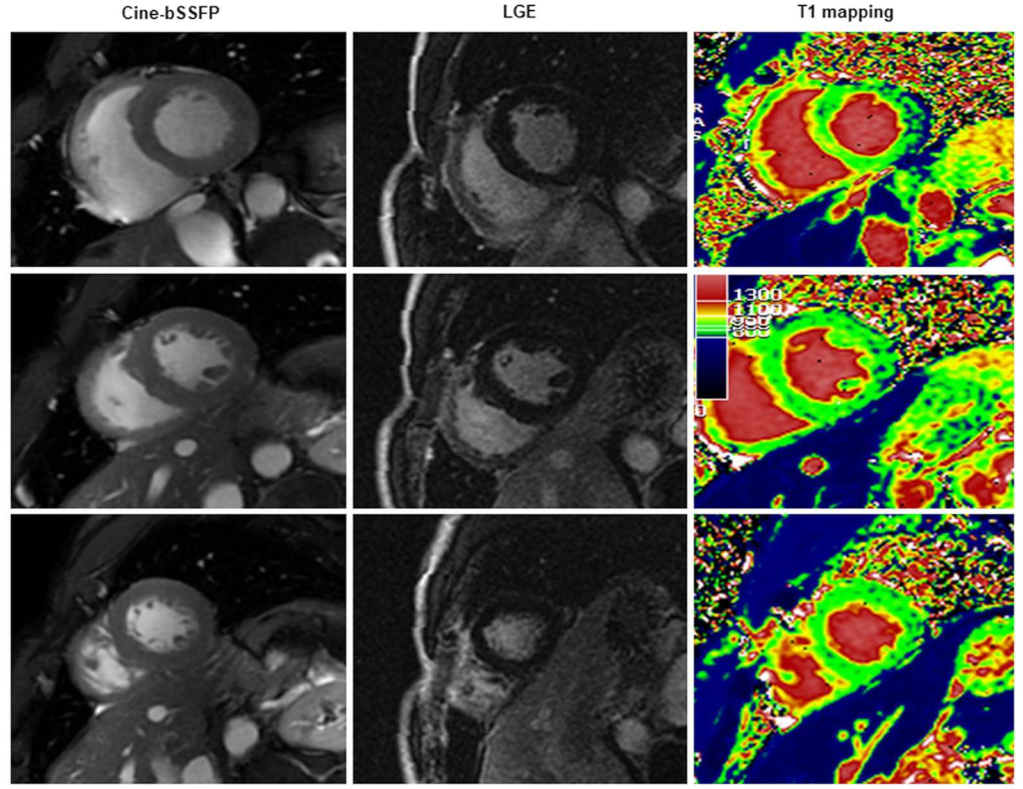

3.1. Conventional CMR vs. T1 Mapping

3.2. Diagnostic Role of T1 Mapping

3.3. Diffuse vs. Regional Myocardial Damage